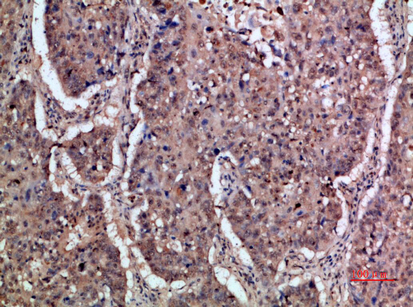

Immunohistochemical analysis of paraffin-embedded human-lung-cancer, antibody was diluted at 1:200